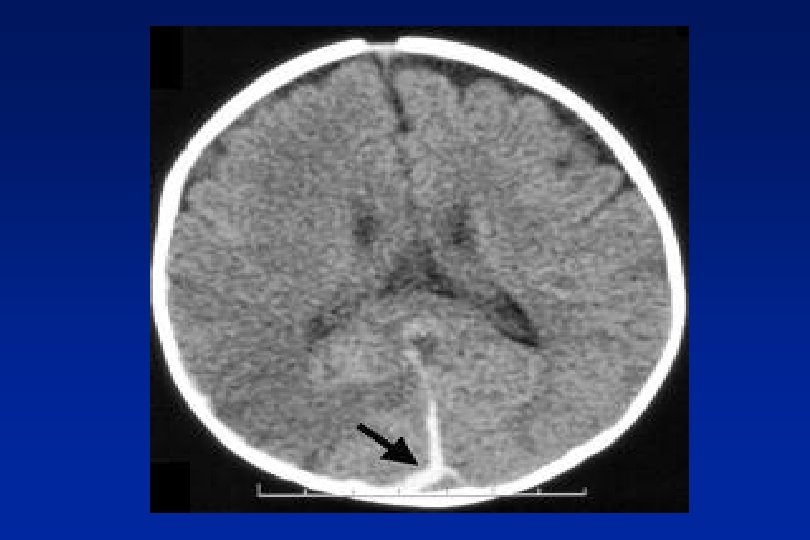

Low Pressure Headache